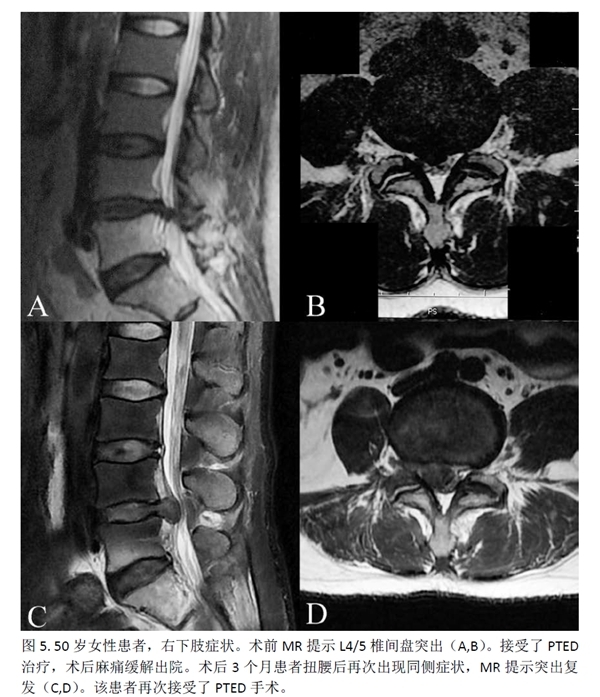

此外,2例(2.5%)PTED组患者及7例(9.59%)MED组患者出现新发患肢麻木感,但两组间没有统计学差异。MED组还有1例(1.36%)患者发生伤口愈合不良。PTED组有5例(6.25%)患者因复发/残留而需进行再次手术,MED组则为3例(4.11%)。再次手术率方面,两组之间没有统计学差异(p=0.818)。